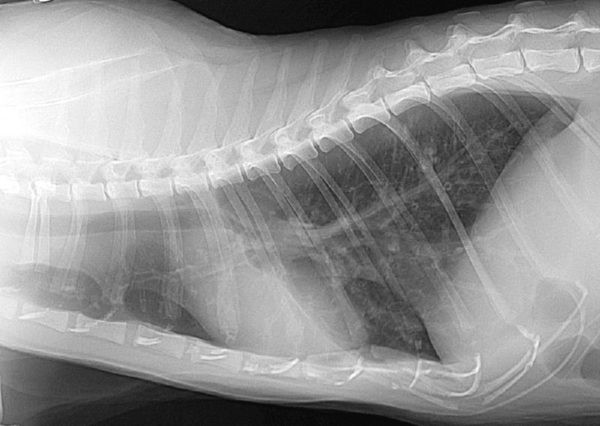

Digital radiography to enhance standard x-ray of a cat's abdomen.

Cat abdomen